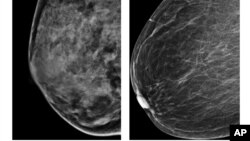

Ko’krak saratonining turli shakllari va bosqichlari bor